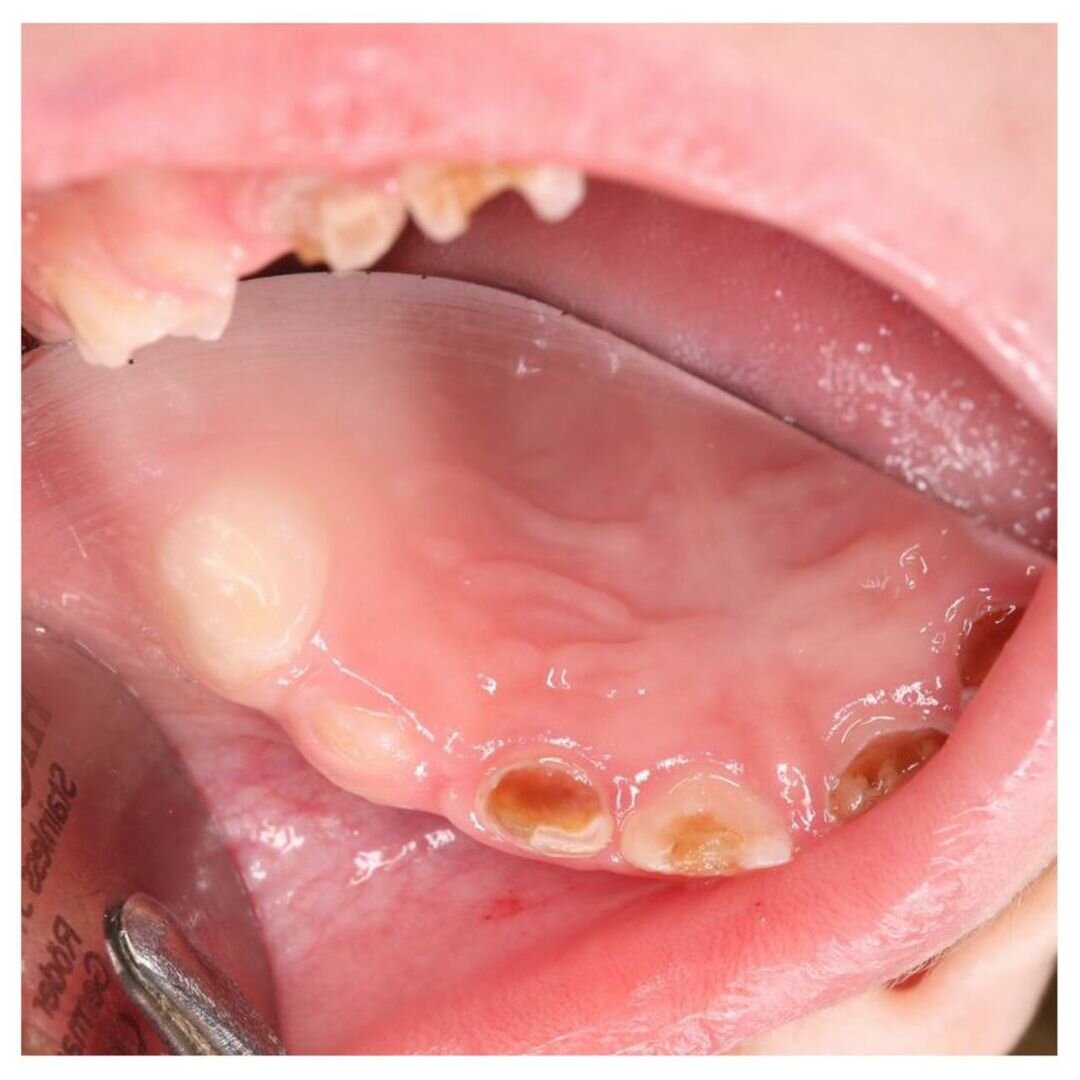

Пришла мама с малышом (1 г 10 мес).

В августе его лечили под наркозом в другой клинике.

Были вылечены, внимание❗ Только 3 жевательных зуба❗

Врач не трогал передние и сказал, что лечить их не нужно, пусть гниют, а когда появятся свищи, тогда и удалите...

В полости рта маленького пациента остались разрушенные, пораженные кариесом, зубки.

Это постоянный очаг инфекции!

Воспаление может распространиться вглубь, поразить периодонт и зачатки постоянных зубов!

На приеме мы сделали снимки — лечить нужно срочно.

Центральный верхний резец под вопросом: удалять или еще можно спасти.